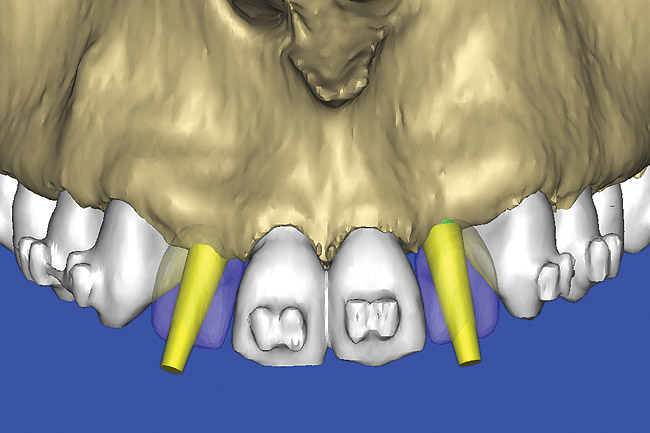

Figure 12  SOFTWARE IMAGING The 3D reconstruction showed the facial concavities and root eminences.

Figure 12

Figure 13  SOFTWARE IMAGING This allowed for evaluation of virtual implant placement to ensure the facial cortical plate was not perforated.

Figure 13

After the basic plan had been established, it was re-evaluated using interactive 3D images. The reconstructed 3D view of the maxilla clearly illustrated the extent of the bilateral facial concavities, and the root eminences of the adjacent and posterior teeth (Figure 12). The placement of the virtual implants then was evaluated to ensure that the facial cortical plate was not perforated (Figure 13). The implants were labeled individually as “7” and “10,” with the simulated yellow abutment projection indicating the facial-lingual inclination through the bone to the level above the incisal edge of adjacent teeth. The ability to gain a better understanding of these individual root forms cannot be underestimated. The dental literature has suggested certain parameters for placing implants near teeth and implants next to other implants. However, there is little scientific 3D documentation to support these suggested rules.5-10 The use of an interactive treatment-planning software application permits closer scrutiny of previously difficult-to-visualize areas, and can now be used to redefine perceptions of spatial positioning of implants, especially when in close proximity to natural tooth roots, vital anatomy, and adjacent implants.27-29